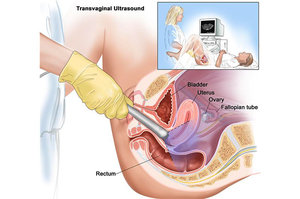

Transvaginal Ultrasonido

Endovaginal Ultrasonido

ENDOVAGINAL ULTRASONIDO $450